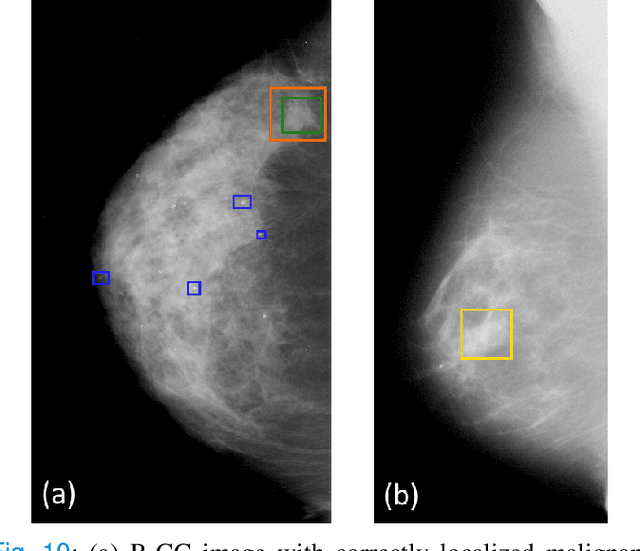

Abstract:The success of machine learning methods for computer vision tasks has driven a surge in computer assisted prediction for medicine and biology. Based on a data-driven relationship between input image and pathological classification, these predictors deliver unprecedented accuracy. Yet, the numerous approaches trying to explain the causality of this learned relationship have fallen short: time constraints, coarse, diffuse and at times misleading results, caused by the employment of heuristic techniques like Gaussian noise and blurring, have hindered their clinical adoption. In this work, we discuss and overcome these obstacles by introducing a neural-network based attribution method, applicable to any trained predictor. Our solution identifies salient regions of an input image in a single forward-pass by measuring the effect of local image-perturbations on a predictor's score. We replace heuristic techniques with a strong neighborhood conditioned inpainting approach, avoiding anatomically implausible, hence adversarial artifacts. We evaluate on public mammography data and compare against existing state-of-the-art methods. Furthermore, we exemplify the approach's generalizability by demonstrating results on chest X-rays. Our solution shows, both quantitatively and qualitatively, a significant reduction of localization ambiguity and clearer conveying results, without sacrificing time efficiency.

Abstract:Clinical applicability of automated decision support systems depends on a robust, well-understood classification interpretation. Artificial neural networks while achieving class-leading scores fall short in this regard. Therefore, numerous approaches have been proposed that map a salient region of an image to a diagnostic classification. Utilizing heuristic methodology, like blurring and noise, they tend to produce diffuse, sometimes misleading results, hindering their general adoption. In this work we overcome these issues by presenting a model agnostic saliency mapping framework tailored to medical imaging. We replace heuristic techniques with a strong neighborhood conditioned inpainting approach, which avoids anatomically implausible artefacts. We formulate saliency attribution as a map-quality optimization task, enforcing constrained and focused attributions. Experiments on public mammography data show quantitatively and qualitatively more precise localization and clearer conveying results than existing state-of-the-art methods.